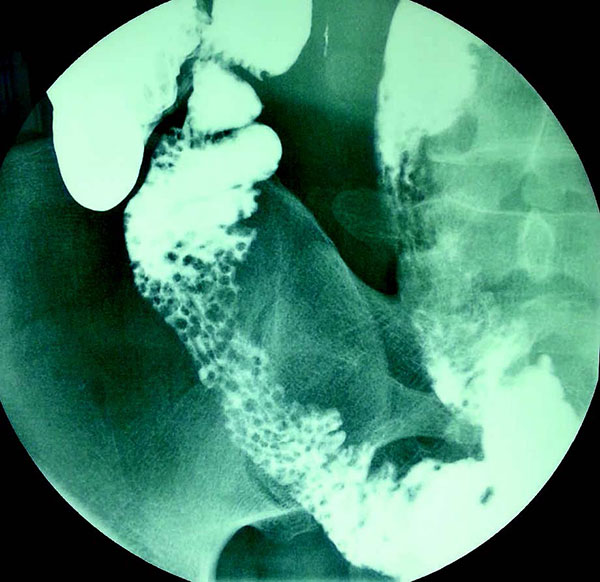

患者男,32岁。12岁时被诊断为复发性鼻窦炎、支气管炎和扁桃体炎。患者自述腹泻2周余。影像学示结节性淋巴组织增生:

下列哪种疾病可出现这些特殊的影像学图片?

答案:B